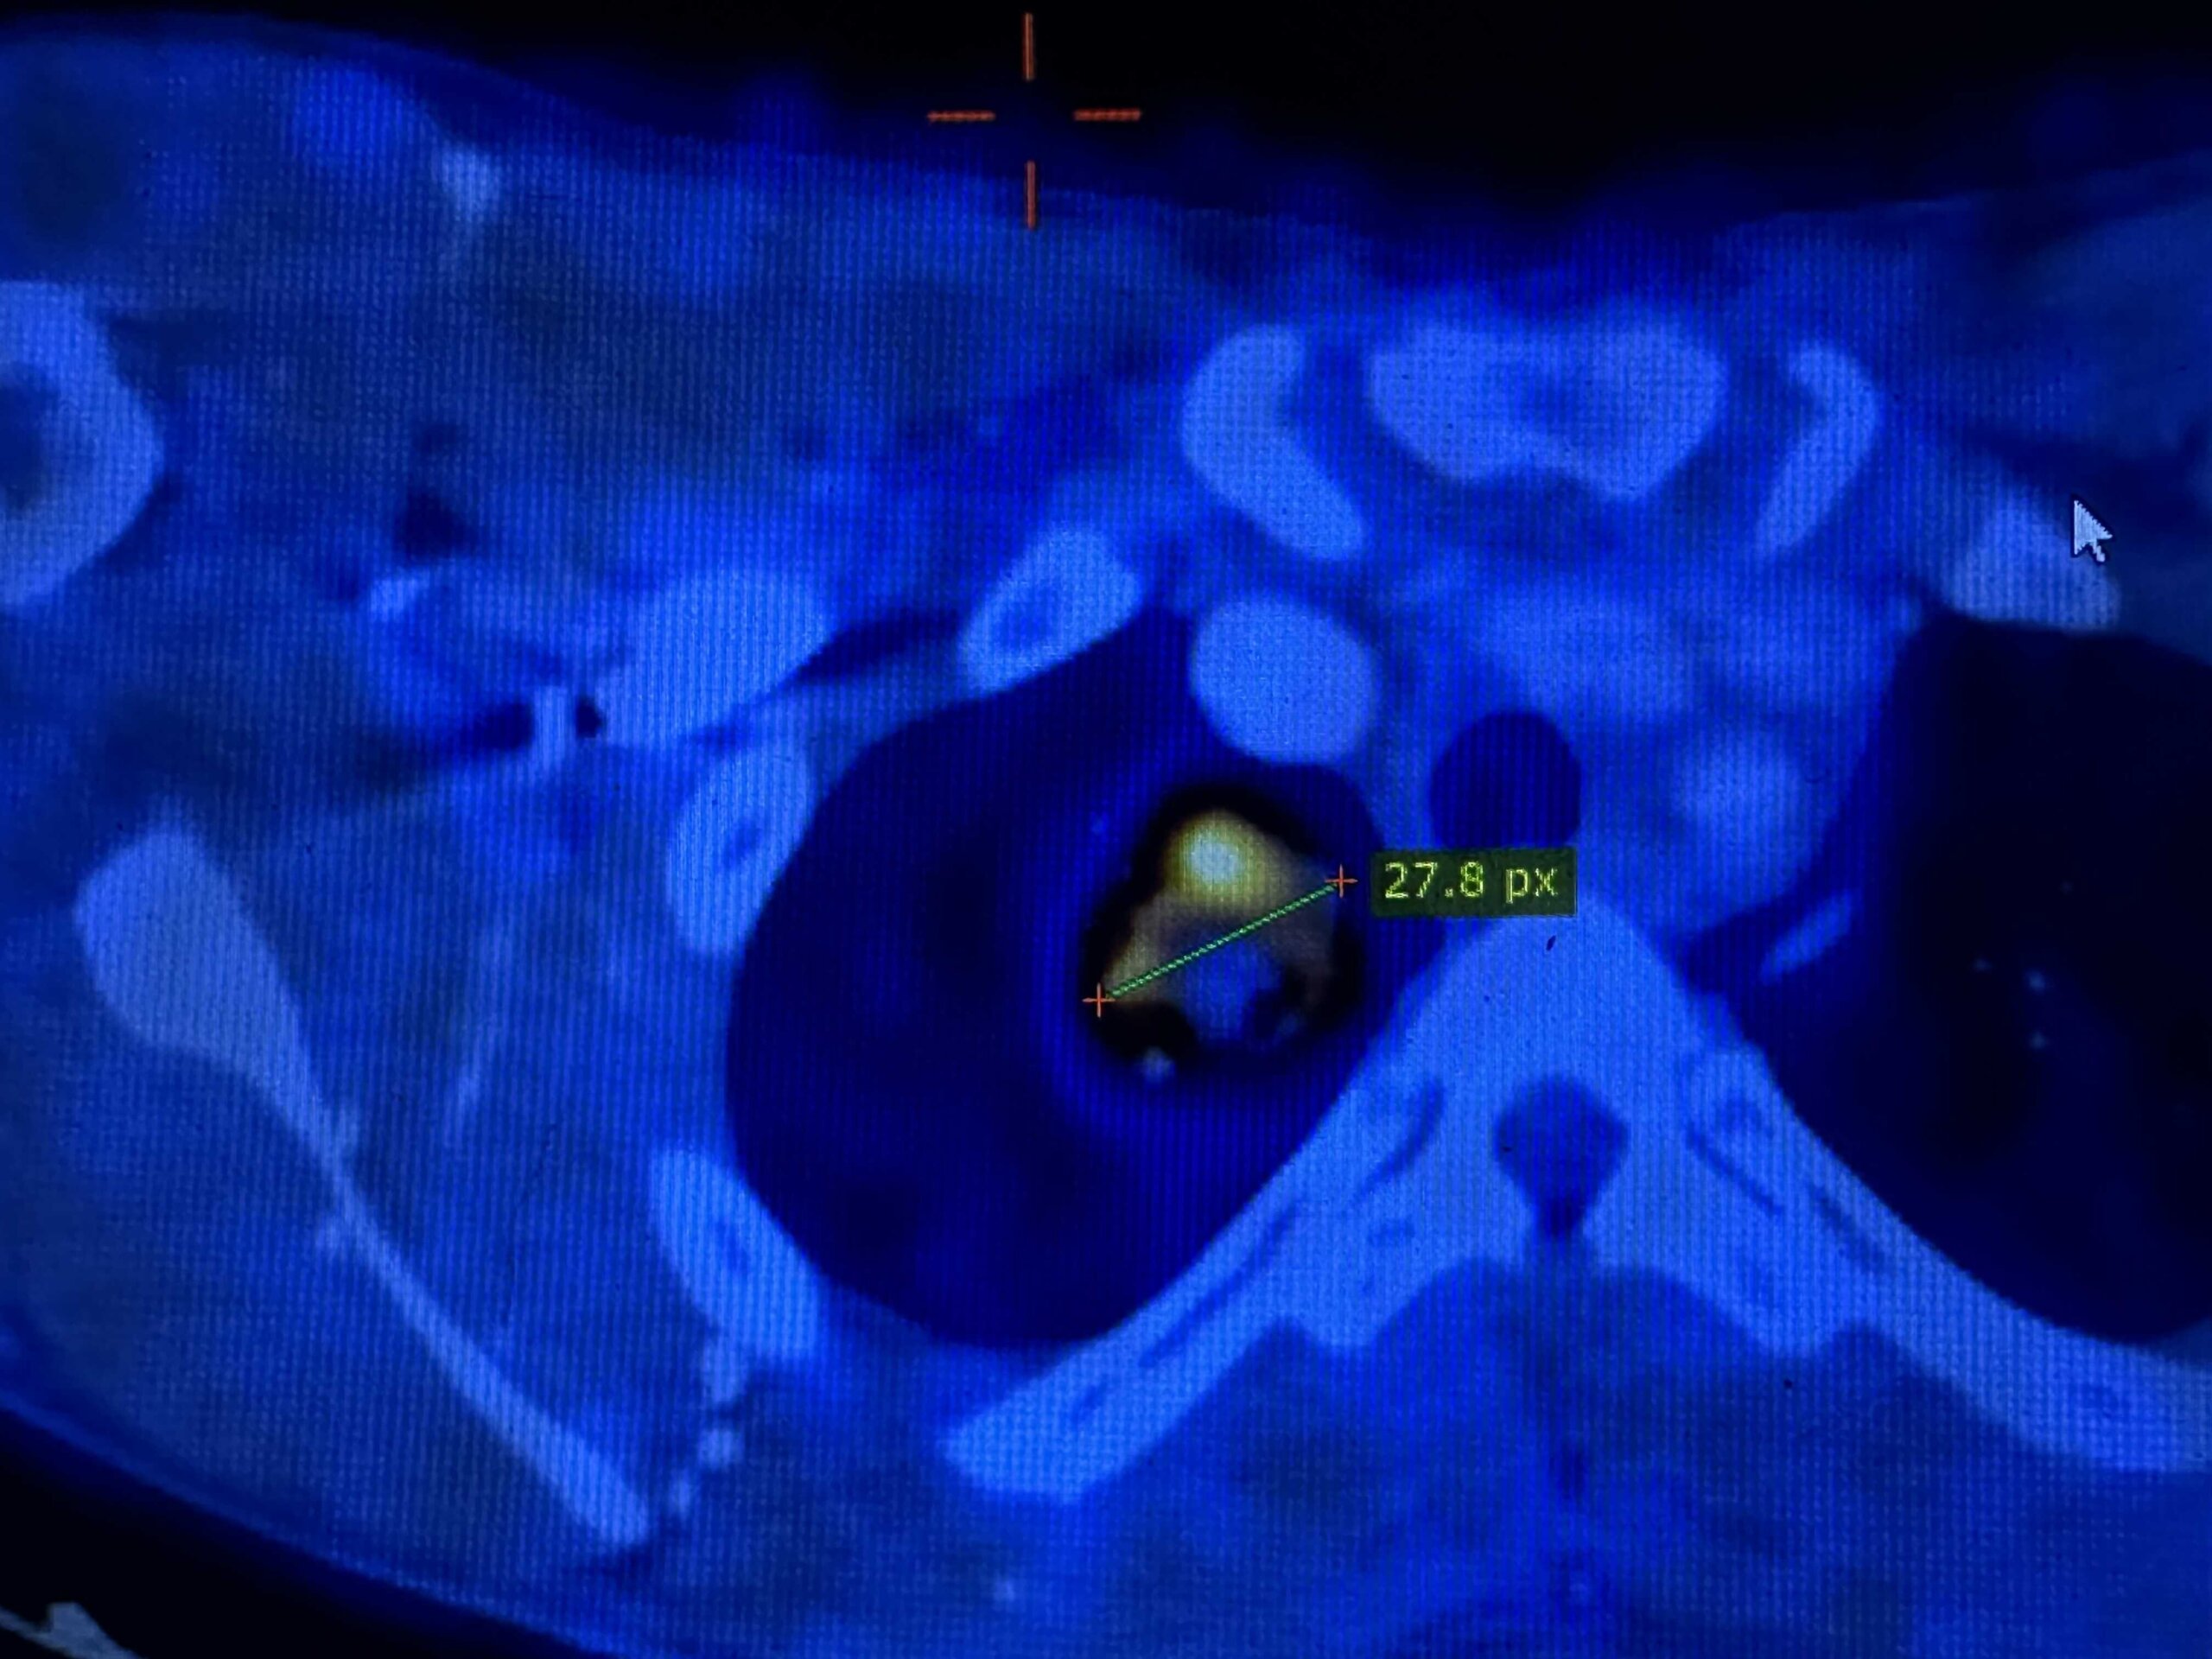

הביולוגיה של HNSCC

הבסיס הנדרש להבנת סרטן ראש-צוואר. מתחילים מהיסוד, עולה בהדרגה